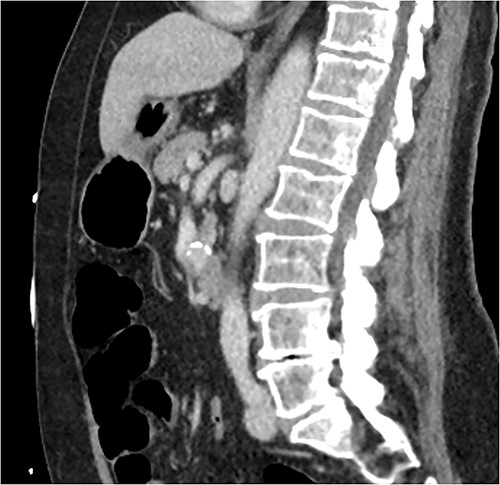

CT of abdomen and pelvis was performed, which revealed a 13 mm indeterminate lesion arising between the pancreatic uncinate process and the duodenum with coarse peripheral calcification, suspicious of primary pancreatic neoplasm or primary small bowel cancer (Figs 2–4).

Initial CT: sagittal view of the indeterminate pancreatic/duodenal lesion.